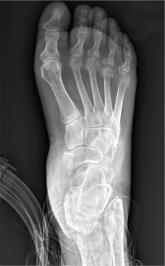

A 51-year-old man is brought to your facility for evaluation of right foot pain after sustaining a fall. He was working on top of his house when he lo...